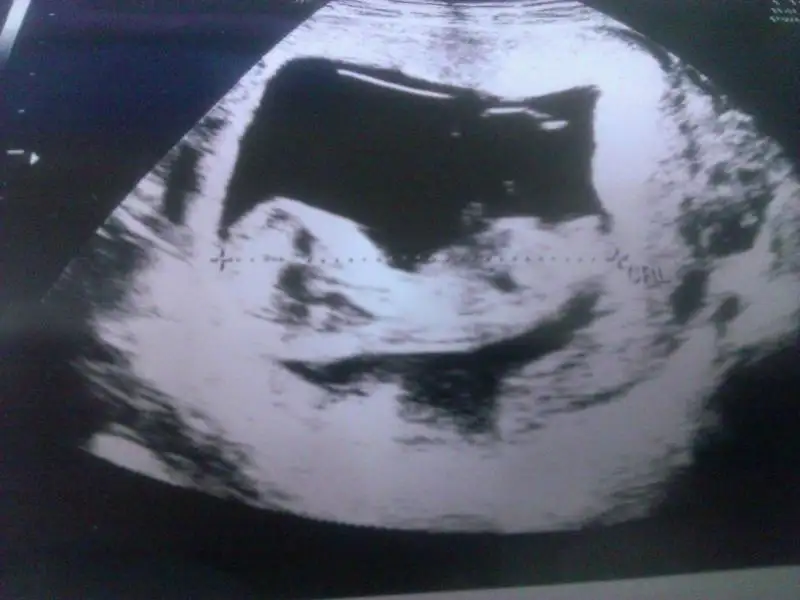

Ben de burdan size soriyim dedim usta gözler bi göz atsanız benim limonuma pek bi seviniriz:) 12+4 görünüyoruz burda :)

Eki Görüntüle 1211261 hocam benim için de bir bakar mısınız? 12 hafta 6 gunluk sonucumuz ... doktor bir şe demedi erken dedi...

kızlar birde benim bebişime bakın bakalımmmm :) Dün doktora gittik 10+3 günlük 2 hafta sonra 2li test yapılcak ve doktor büyük ihtimal cinsiyeti belli olur dedi..Ama herkes gibi bende çok merak ediyorum tabi öncelikle beden ve zihin sağlığı ama insan hep merak eder ya :) yorumları bekliyorum şimdiden teşekkürlerrrr